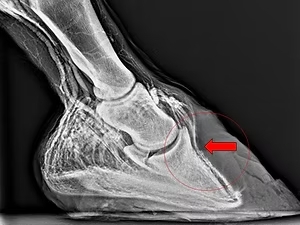

„Venographie der distalen Zehe“ von Dr. Mark Zengerling

Dr. Mark Zengerling hat am 08. November 2019 bei der Fortbildungsveranstaltung mit derbymed-Livisto in unserer Klinik diesen interessanten Vortrag gehalten.

Interessierte können diesen gerne hier nachlesen: Vortrag